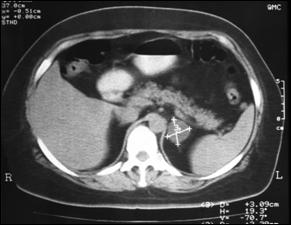

Fig.25. Metastaza suprarenaliana dreapta

masiva, cu punct de plecare bronhopulmonar - aspect TC. Fig.26. Voluminoasa metastaza suprarenaliana

stânga, cu tromboza extensiva de vena renala

stânga si vena cava inferioara - aspect TC.